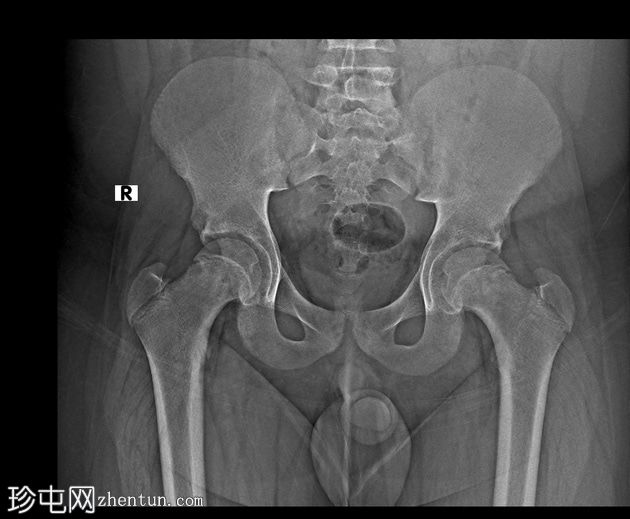

X线片

正位片

双侧股骨近端骨骺皮质不规则,轻度增宽。

双侧股骨骨骺轻度后内侧移位。

双侧轻度股骨头骨骺滑脱(SCFE)属于Salter-Harris I型骨折,由于没有正常侧可供比较,因此在X线片上容易被漏诊。

之所以称之为轻度,是因为骨骺外侧缘仍位于干骺端外侧三分之一处。